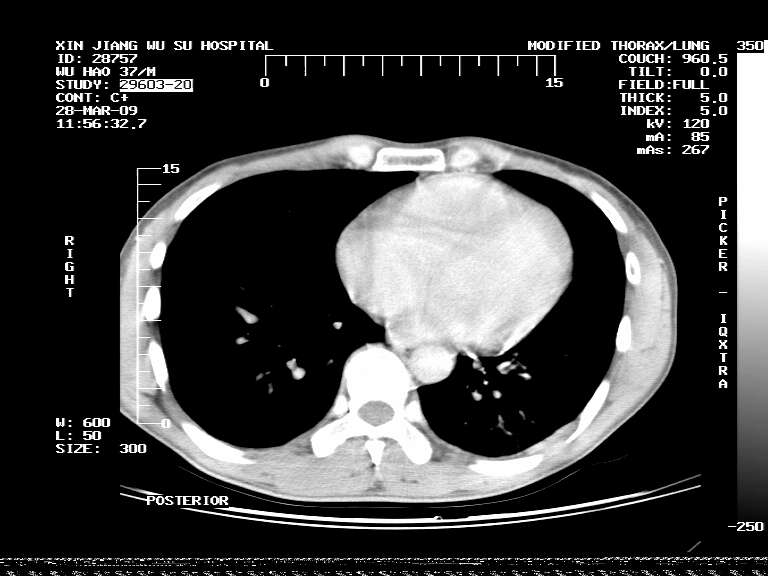

男,37岁,体检胸透发现阴影。

患者体检发现 无症状 左肺下叶占位,边缘模糊,可见血管聚束、分叶、胸膜牵拉,增强呈不均匀性强化。 首先考虑左肺下叶周围型肺癌,建议穿刺活检。

左肺下叶见一结节病变,边缘欠清不光滑,与胸膜粘连且胸膜局限性增厚,注药后呈环形强化,动脉期壁呈明显点环状强化,静脉期壁强化减低,中心密度低无强化,灶周无明显的卫星灶和水肿区(晕征)---考虑周围性肺癌,不除外感染性病变,建议穿刺活检。

左肺下叶软组织病灶,密度较高,内见点状钙化,其周围见子灶,邻近胸膜扁平样增厚.c+病灶强化明显,中心强化弱.诊断:左肺下叶结核瘤.

左肺下叶大片实变影,内靠胸膜见不规则更高密度结节灶,边缘强化,相邻胸膜增厚,胸膜下脂肪线存在。考虑炎症,结核可能。